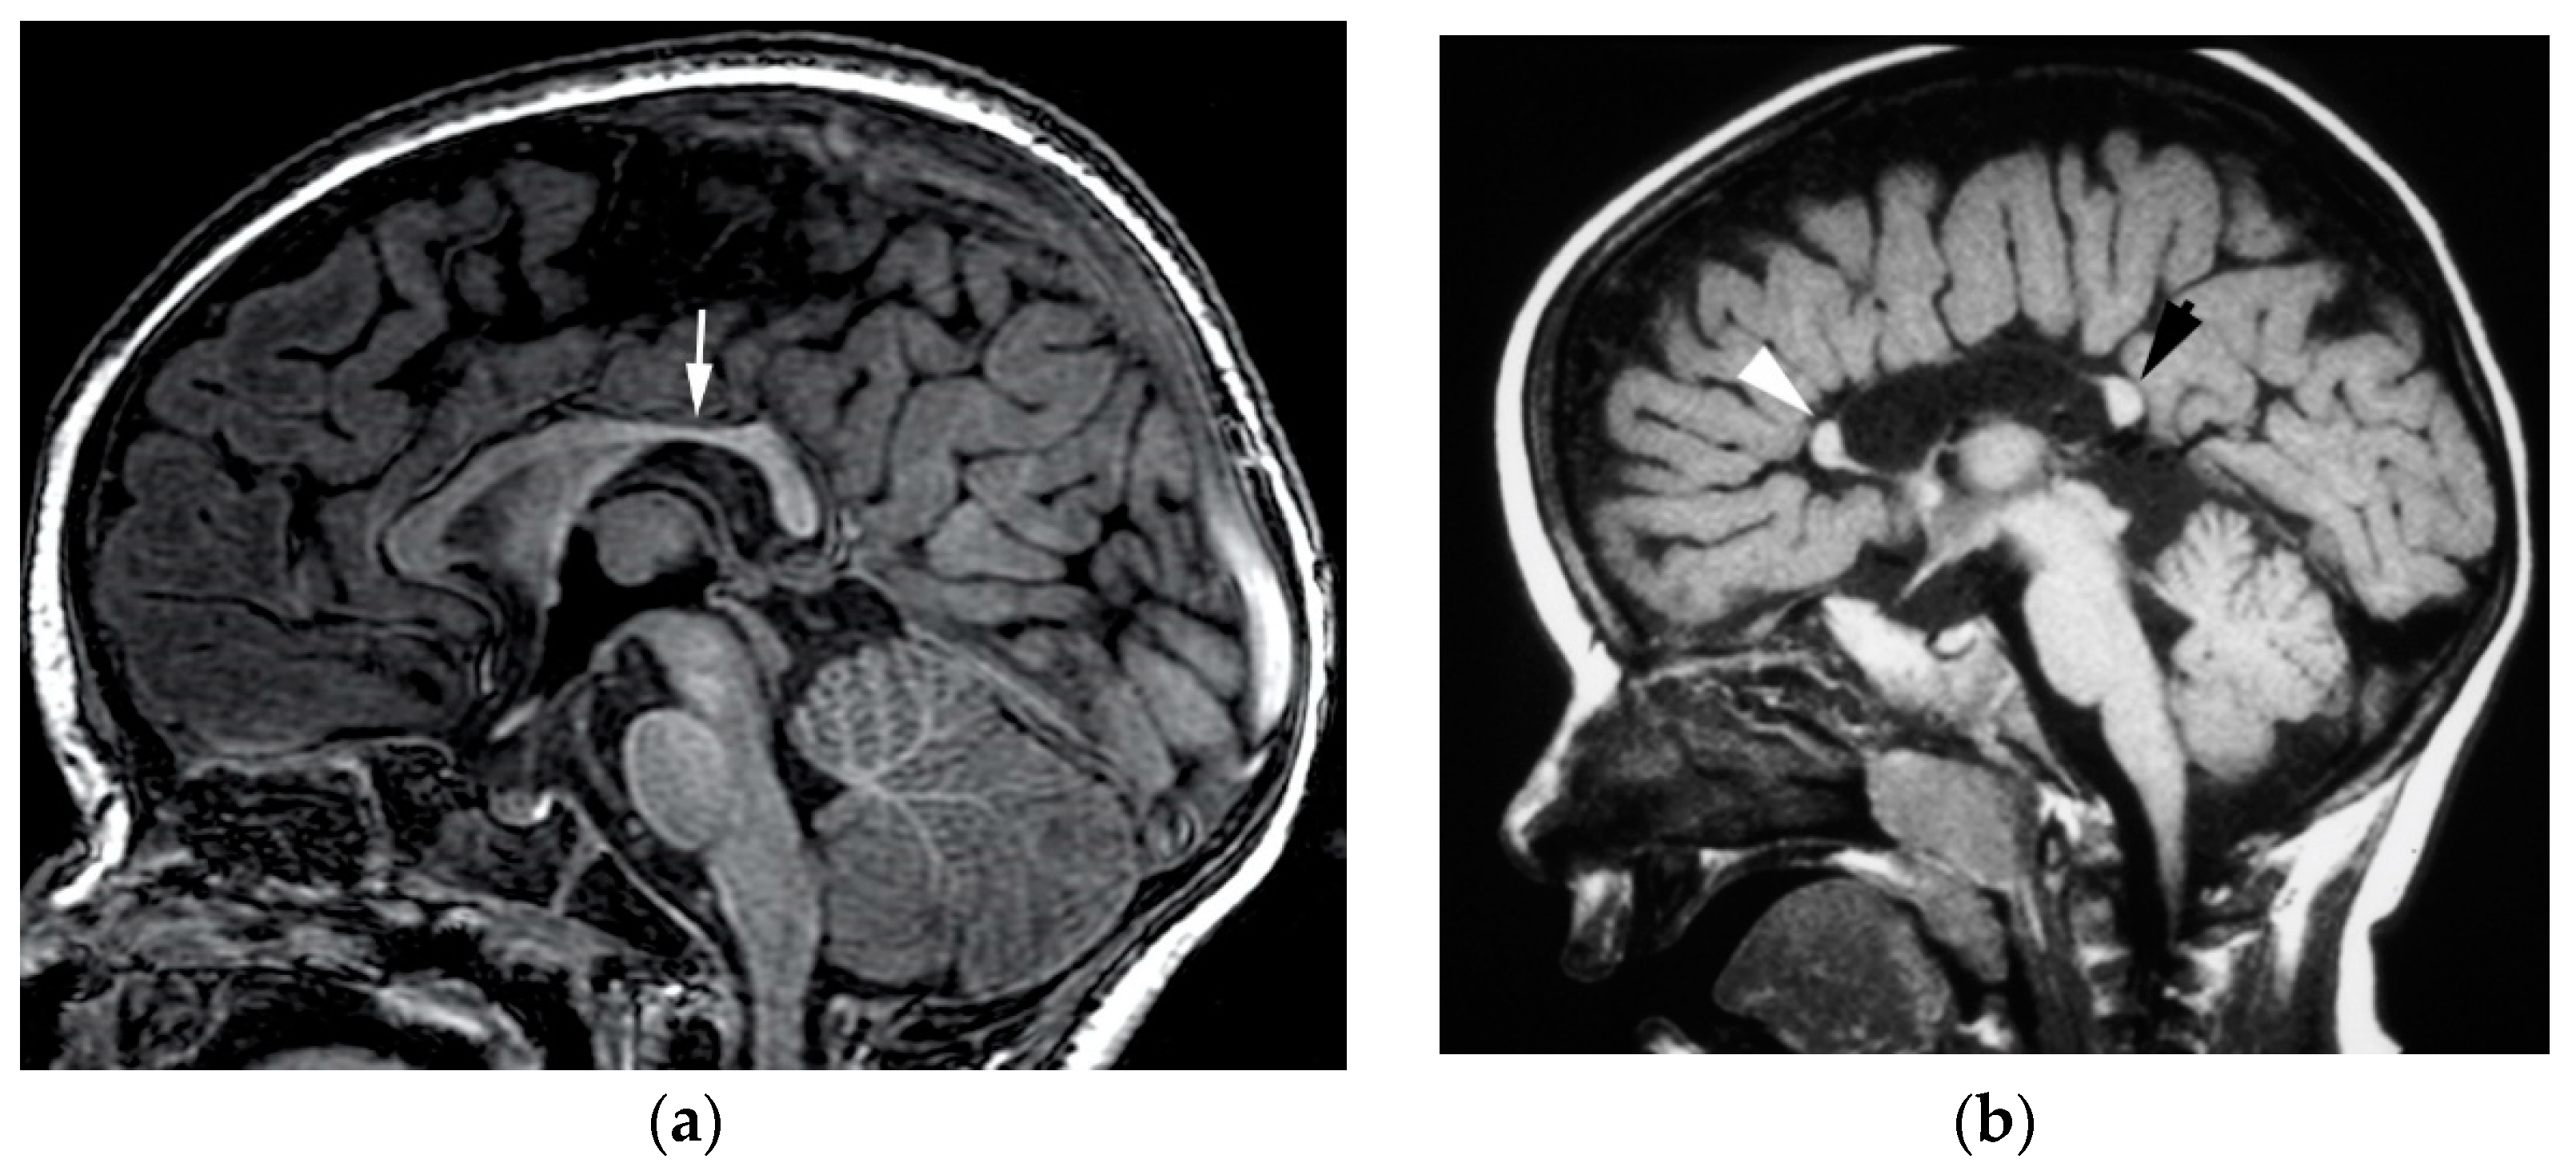

3.5. Agenesis of the Corpus Callosum

3.6. Hypogenesis of the Corpus Callosum